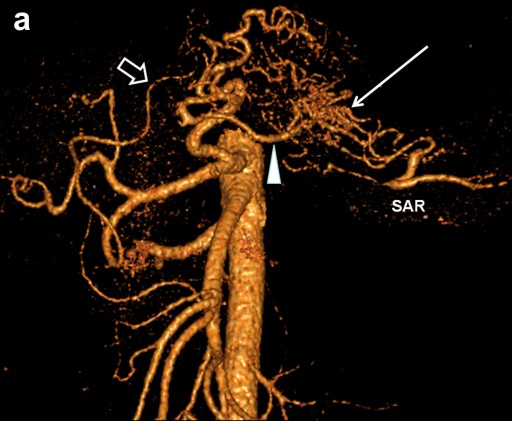

Preceding surgery, the splenic artery was always seen on CT angiography as a thick stem with no other branches travelling to the spleen (Figures 7a and 8a). As a consequence of splenic artery resection, the whole or the bulk of its trunk were no longer available for evaluation by CT angiography after a spleen-preserving distal pancreatectomy with resection of the splenic vessels and, in all 10 cases, the gastroepiploic arcade was seen to have become the “highway” to the spleen within 7-30 days after surgery (Figures 7b, 8b, and 9). In two cases, due to technical reasons, 3D CT angiography was only carried out postoperatively but, in both cases, there were no doubts about the source of the blood supply to the spleen (Figure 9). In none of the 10 cases was any appreciable blood flow through the short gastric arteries visualized.

Figure 7. Celiaco-mesenterial anatomy in а 53-year-old man with chronic pancreatitis of the distal type. 3D CT angiography after the renal artery images were eliminated. Vertical view. a. Before surgery: the splenic artery thick trunk with no collaterals is shown. b. Fourteen days after a spleen-sparing distal pancreatectomy with resection of the splenic vessels: the spleen is fed through the gastroepiploic arcade. There are no other detectable major arteries to feed the spleen. D: drainage tube; GEA: gastroepiploic arcade; RGEA: right gastroepiploic artery; SA splenic artery; SAR: splenic artery remnant |